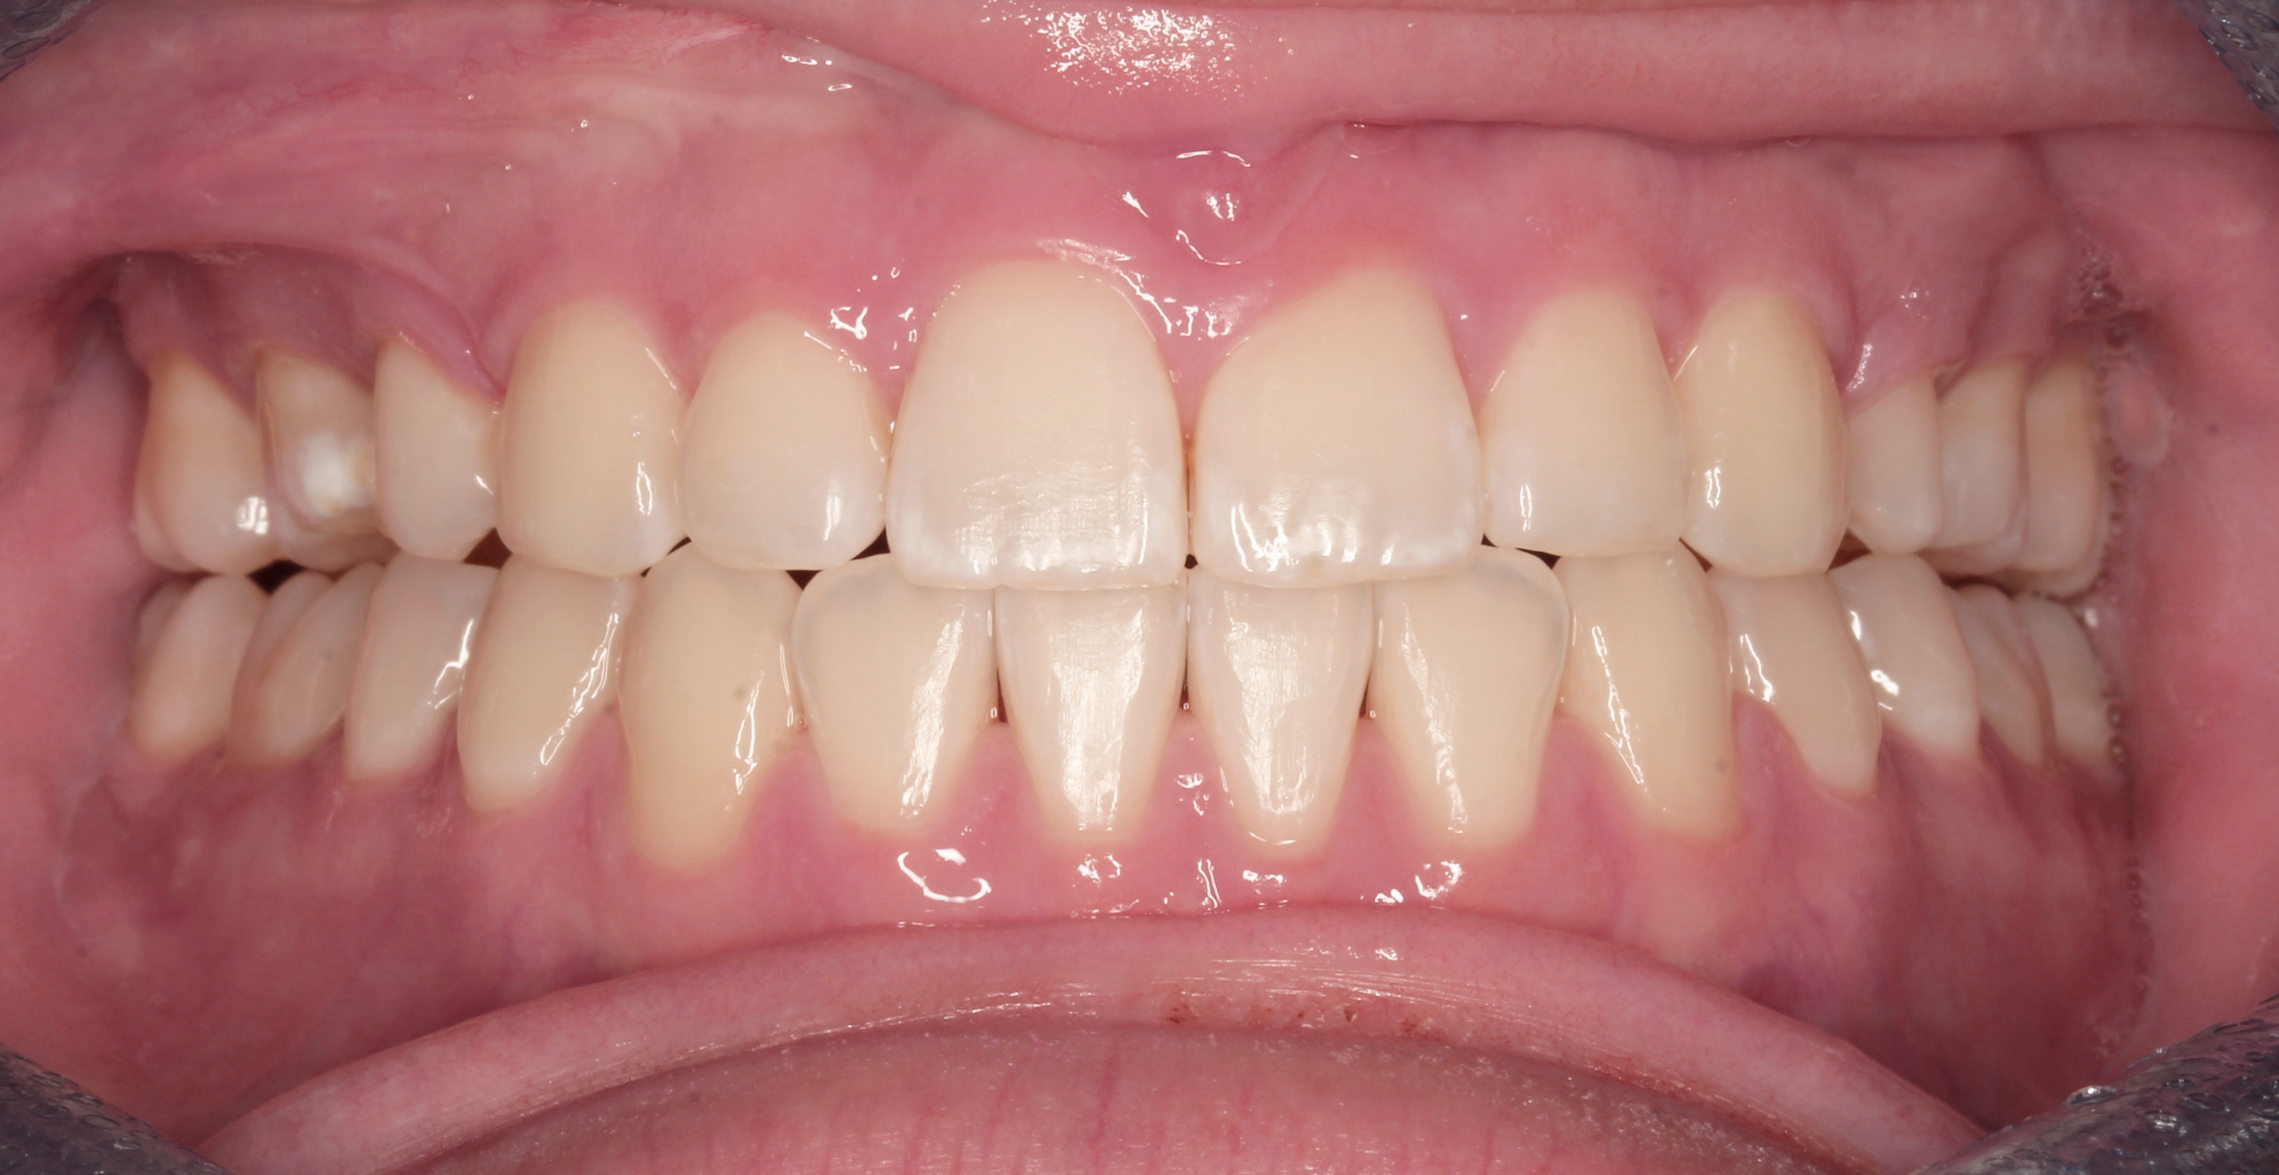

Before teeth alignment comparison: Intraoral before photo of Metal Self-Ligating Braces & Orthognathic Surgery showing the intraoral records reveal the magnitude of this correction. Before

This case began with a severe skeletal imbalance that braces alone could not correct. The patient presented with a significant Class III bite, asymmetric mandibular prognathism, anterior crossbite, and midline deviation. Because the jaw relationship was the root of the problem, a combined orthodontic and surgical approach was required to achieve the best stable, long-term result.

This transformation was designed with intention. Dr. Benson used braces to sculpt alignment and prepare the bite, then collaborated with an oral surgeon to reposition the mandible through orthognathic surgery. The result: a stable bite, restored facial balance, and symmetry achieved.